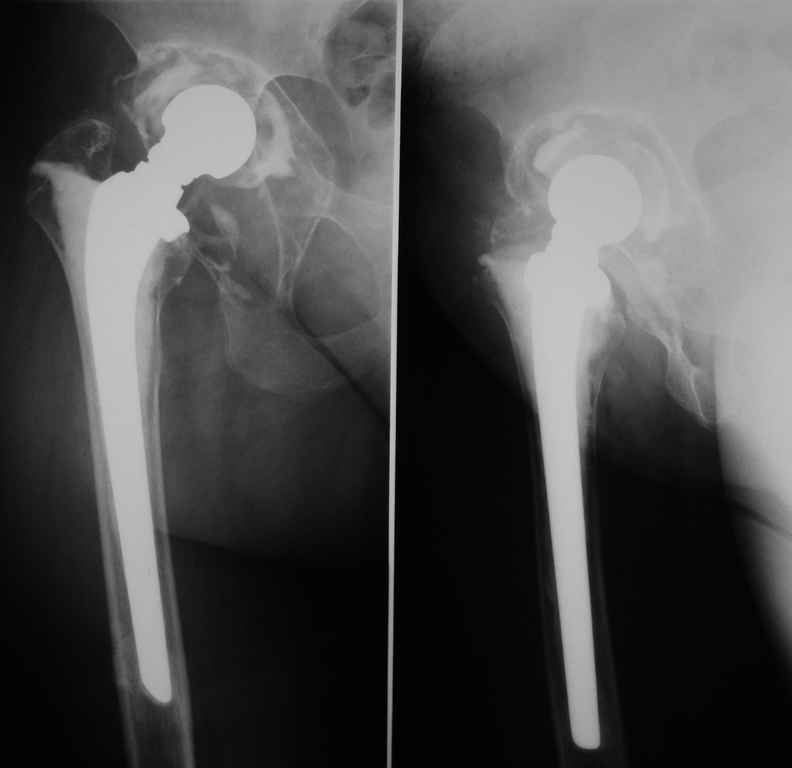

Больная 40 лет, поступила в отделение с диагнозом: Нестабильность чашки цементного эндопротеза Мовшовича правого тазобедренного сустава с протрузией тазового компонента.

Рентгенограммы от 07,07,2009г.

Данных за нестабильность ножки не выявлено. Помогите определиться с выбором оптимального варианта ревизии:

1 вариант

Планируем использовать кольцо Бурх—Шнайдера большого размера 60 (внутренний диаметр) и аллотрансплантат для пластики дна впадины и тела седалищной кости, чтобы получить возможность фиксации нижней клиновидной части кольца и уменьшить размер дефекта. 2 вариант

пластика вертлужной впадины массивным аллотрансплантатом с установкой в него цементной чашки.